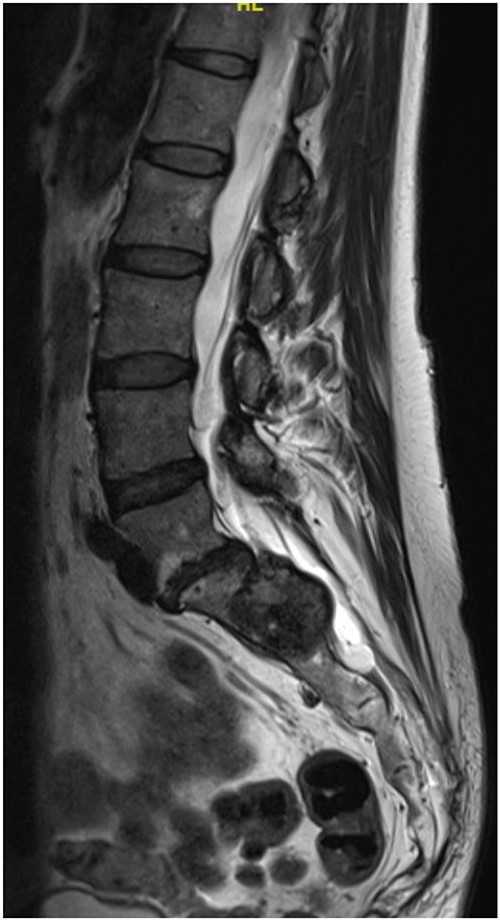

Reviews in July 2019 (with an MRI scan in December 2019) and December 2020 confirmed no neurological deterioration but some increased back and leg pain when standing for some time. A repeat MRI scan confirmed an increase in the size of the lesion (Figs 1 and 2). A biopsy was arranged with a plan for a follow-up surgery. Results of the CT-guided biopsy indicated a diagnosis of metastatic malignant melanoma. Discussions with the patient did not localise any skin lesion responsible for the metastatic deposit, an F18-fluorodeoxyglucose positron emission tomography (18F-FDG PET/CT) scan and a conventional computed axial tomography (CT) scan was organised (April 2021), which revealed sacral destruction and no other deposits in the chest, abdomen and pelvis (Figs 3 and 4). Our patient had a reported SUV of 3.6, indicating a malignant lesion that was then confirmed operatively.

MS comprises <1% of primary peripheral sheath tumours. The most common sites are cervical and upper thoracic spinal nerves with 30–40 years being the most common age group of occurrences [1, 3, 9]. The MRI characteristics of high signal on T1WI and low signal on T2WI with homogenous enhancement with contrast are well known. Our patient was in an older age group during presentation and had no skin deposits. Whereas a diagnosis was made on biopsy, it is also possible to use the FDG uptake on PET/CT imaging to determine the benign or malignant nature of the tumour [1]. The standardised uptake value (SUV) is a simple way of determining activity in PET imaging, most commonly in FDG imaging, and can predict the histologic response [10, 11]. It is used to measure response of cancers to treatment and considered a semi-quantitative value as it is vulnerable to other sources of variabilities [10, 11]. Hamada et al. set the cut-off point to 3.0 for distinguishing benign and malignant lesions [12]. Whereas there is an overlap in the SUV cut-off point amongst various authors, there is also a wide variation between them [13, 14]. Ahmed et al. reported 0.33–3.7, whereas Aoki et al. reported 1.75 ± 0.84 [14, 15]. However, Aoki et al., in another paper, reported a wider range of 0.7–2.84 [13]. Our patient had a reported SUV of 3.6, indicating a malignant lesion that was then confirmed operatively.